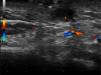

The patient was a 32-year-old man with no past history of interest. He was seen in dermatology outpatients for a tumor in the form of a cutaneous horn sunken into the skin over the left horizontal ramus of the mandible (Fig. 1). Examination revealed no alterations of the oral cavity. The patient stated that the region was tender. He had applied topical treatment with 2% mupirocin ointment without improvement. B mode skin ultrasound (Esaote, Genoa, Italy) using an 18MHz probe revealed a slightly tortuous, relatively well-defined, hypoechoic linear structure that extended to the surface of the cortical bone of the mandible (Fig. 2). Doppler study showed blood vessels in the area around the tract, suggestive of inflammation, and a poorly defined hypoechoic outline in B mode (Fig. 3). With a diagnosis of cutaneous odontogenic sinus, the patient was referred to the maxillofacial surgery department, where the study was completed with orthopantomography. This x-ray study revealed a radiolucent image that surrounded the apex of the posterior root of the left first molar (Fig. 4). Conservative treatment was performed with endodontia and restoration with an amalgam filling, leading to resolution of the cutaneous sinus in 20 days.

Recently, Shobatake et al.5 published 3 cases of cutaneous odontogenic sinuses diagnosed by ultrasound. Dermatologic ultrasound shows a well-recognized pattern with a relatively well-defined, linear but slightly tortuous, hypoechoic sinus tract that is seen to reach the surface of the cortical bone; Doppler reveals a variable degree of vascularization. Ultrasound is a tool that complements other radiologic techniques and requires little time to perform. It is an excellent option to facilitate the diagnosis of this type of lesion, even for dermatologists with little experience in the management of oral pathology. In addition, it can be used to monitor therapy and to evaluate the associated inflammation to help determine a possible indication for antibiotic prophylaxis prior to intervention.